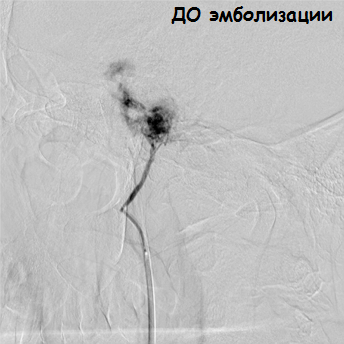

— Мы пытались удалить опухоль стандартным хирургическим путем, но до конца нам сделать это не удалось, — рассказывает заведующий ЛОР-отделением Лилия Алексеевна Мосейкина. — При подходе к основанию опухоли наблюдалось сильное кровотечение из 3-х приводящих сосудов. Было принято решение о прекращении операции и тампонаде барабанной полости. И здесь нам на помощь пришли эндоваскулярные хирурги. Ангиография подтвердила сосудистый характер опухоли, помогла определить размеры, распространенность и источники кровоснабжения, что позволило судить об объеме предстоящего вмешательства.

— Через бедренную артерию микрокатетер был введен в артерию, непосредственно кровоснабжающую опухоль, — комментирует ситуацию заведующий отделением РХМДиЛ Александр Евгеньевич Ванюков. — Артерия диаметром около 1 мм является ветвью верхнечелюстной артерии, и, на наш взгляд, безопаснее и эффективнее выполнять точную селективную катетеризацию и эмболизацию артерии, питающей опухоль, чем эмболизировать всю верхнечелюстную артерию. Мы выполнили суперселективную эмболизацию путем введения эмболизационного материала размером 700 нм, что привело к полному прекращению кровоснабжения опухоли.